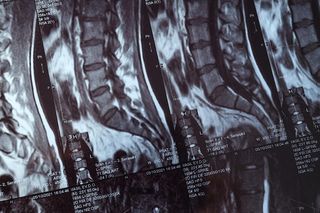

КТ пояснично-крестцового отдела позвоночника

КТ пояснично-крестцового отдела позвоночника — современное диагностическое исследование, направленное на получение послойных снимков сканируемой области высокой четкости и разрешения. Метод применяется для оценки состояния костных тканей позвонков, величины просвета межпозвоночного канала, структуры нервных корешков и конечного участка спинного мозга.

По степени информативности компьютерная томография превосходит рентгенологическое обследование или УЗИ. Она позволяет получить точные данные о природе, локализации и объеме распространения патологического процесса. Процедура максимально комфортна для пациента.